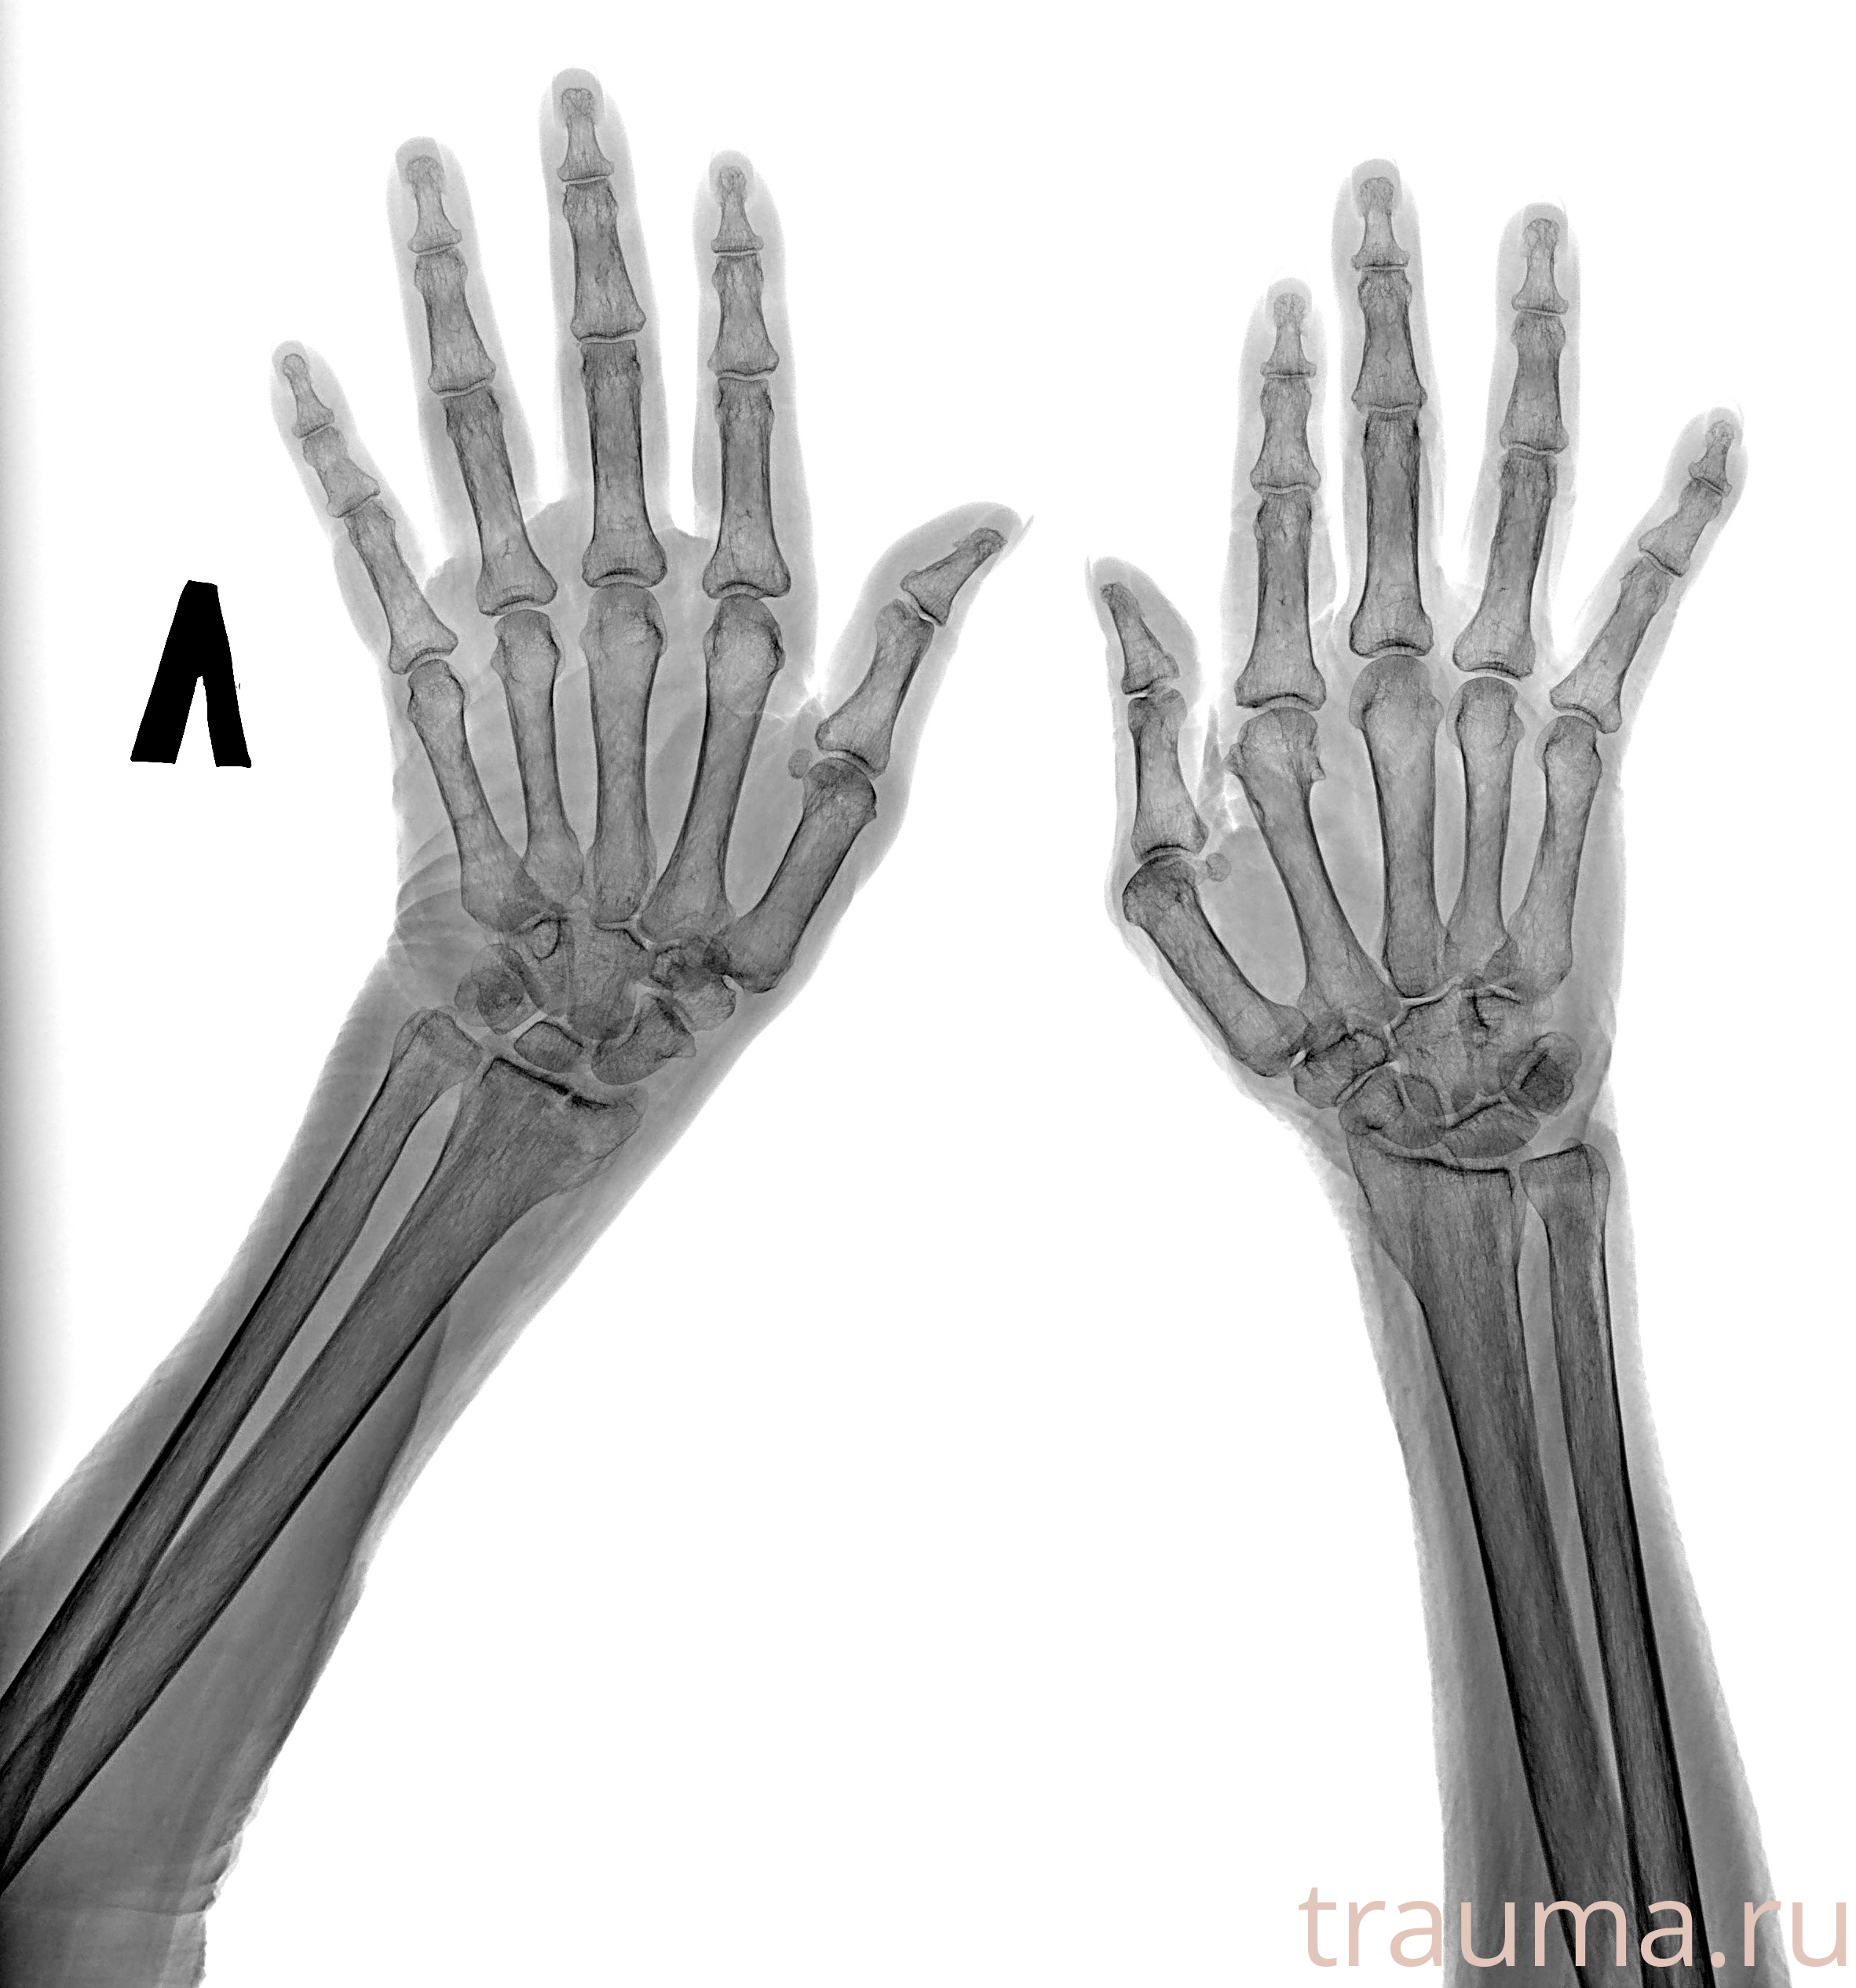

Рентген на дому: по вашему адресу приезжает врач-рентгенолог, травматолог-ортопед с мобильным рентгеновским аппаратом, проводит диагностику травмы или заболевания, делает необходимые рентгенограммы, дает рекомендации по дальнейшему лечению. Получить качественные снимки в домашних условиях возможно благодаря уникальной методике, разработанной МосРентген Центром для института  Склифосовского